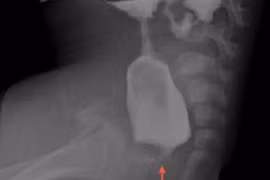

Nội soi điều trị bệnh không hậu môn cho trẻ sơ sinh tại Hải Phòng

Các gia đình nên theo dõi vấn đề đại tiểu tiện của trẻ ngay sau khi sinh, nếu trong 24 giờ đầu không thấy trẻ đại tiện thì cần đưa đến khám tại các bệnh viện.